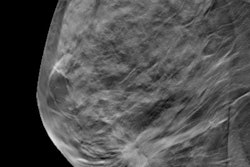

The utility of digital breast tomosynthesis (DBT) as a "safety net" in breast cancer screening will be discussed in this presentation, including its impact on cancer outcomes.In his talk, Dr. Ted Goh from Boston University will show results of his team's study, which compared the performance of DBT with full-field digital mammography in a hybrid screening environment. The researchers analyzed data from 26,250 matched screens, including 13,125 digital mammograms and 13,125 DBT exams performed in 16,060 women.

The study authors found lower recall rates for DBT at 12.1% compared with 14.7% seen in digital mammography. They also found higher specificity for DBT at 88.1% versus 85.7% for mammography. Both data points were statistically significant.

What's more, recall rates and specificity improved with DBT when stratifying women by age group (40-49, 50-59, and 60-69), fatty to heterogeneously dense breast density categories, and baseline exams.

The team also noted no significant differences in cancer detection rate, interval cancer rate, sensitivity, or positive predictive value between groups. Additionally, most invasive and in situ cancers were identified in Black women (50%). The authors noted that about 70% of these were detected by mammography screening.